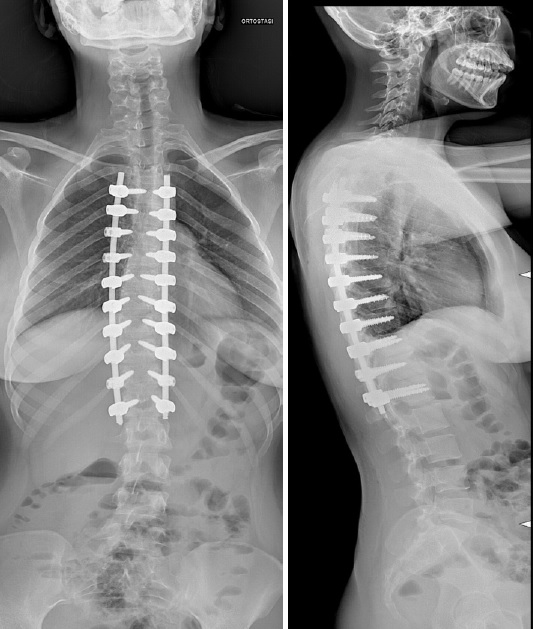

L' intervento che tradizionalmente si propone in questi casi è l’artrodesi posteriore strumentata e prevede l’applicazione di impianti metallici (viti e barre), nelle vertebre che permettono di manipolare la colonna vertebrale e riportarla verso la sua posizione naturale.

Immagine radiografica di artrodesi posteriore

Nell’arco di 6-12 mesi dall’intervento, le vertebre strumentate si fondono tra di loro grazie alla formazione di un callo osseo che rende il costrutto stabile nel tempo.